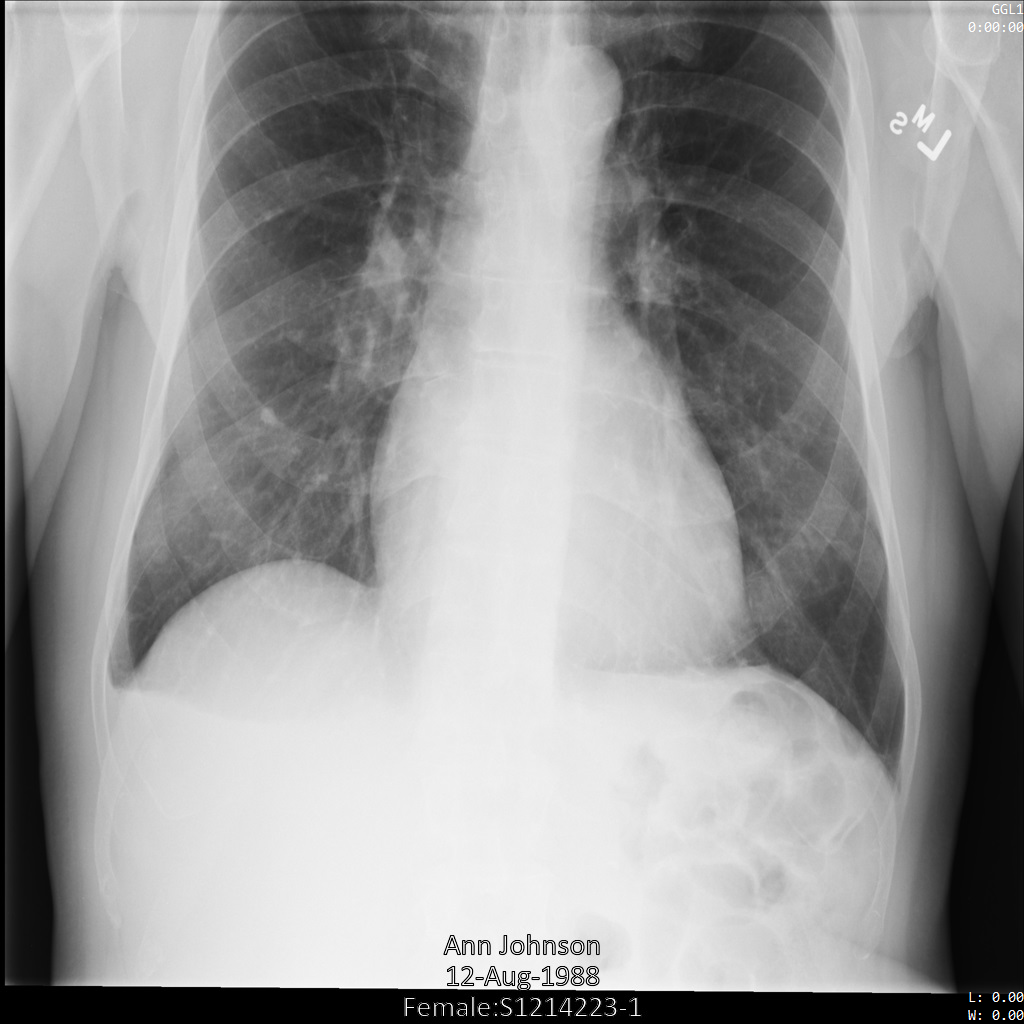

Les exemples suivants montrent comment anonymiser un ensemble de données contenant des magasins DICOM et des données DICOM à l'aide du profil de filtre de tag ATTRIBUTE_CONFIDENTIALITY_BASIC_PROFILE.

Ce profil de filtre de tag supprime les tags en fonction du profil de base de la confidentialité d'attribut du standard DICOM.

Une fois envoyée à l'API Cloud Healthcare à l'aide du profil de filtre de tag ATTRIBUTE_CONFIDENTIALITY_BASIC_PROFILE, l'image apparaît comme suit. Les métadonnées affichées dans les angles supérieurs de l'image ont été masquées, mais les données de santé incrustées en bas de l'image reste affichées.

Pour supprimer également le texte incrusté, consultez la section Masquer le texte incrusté dans les images.